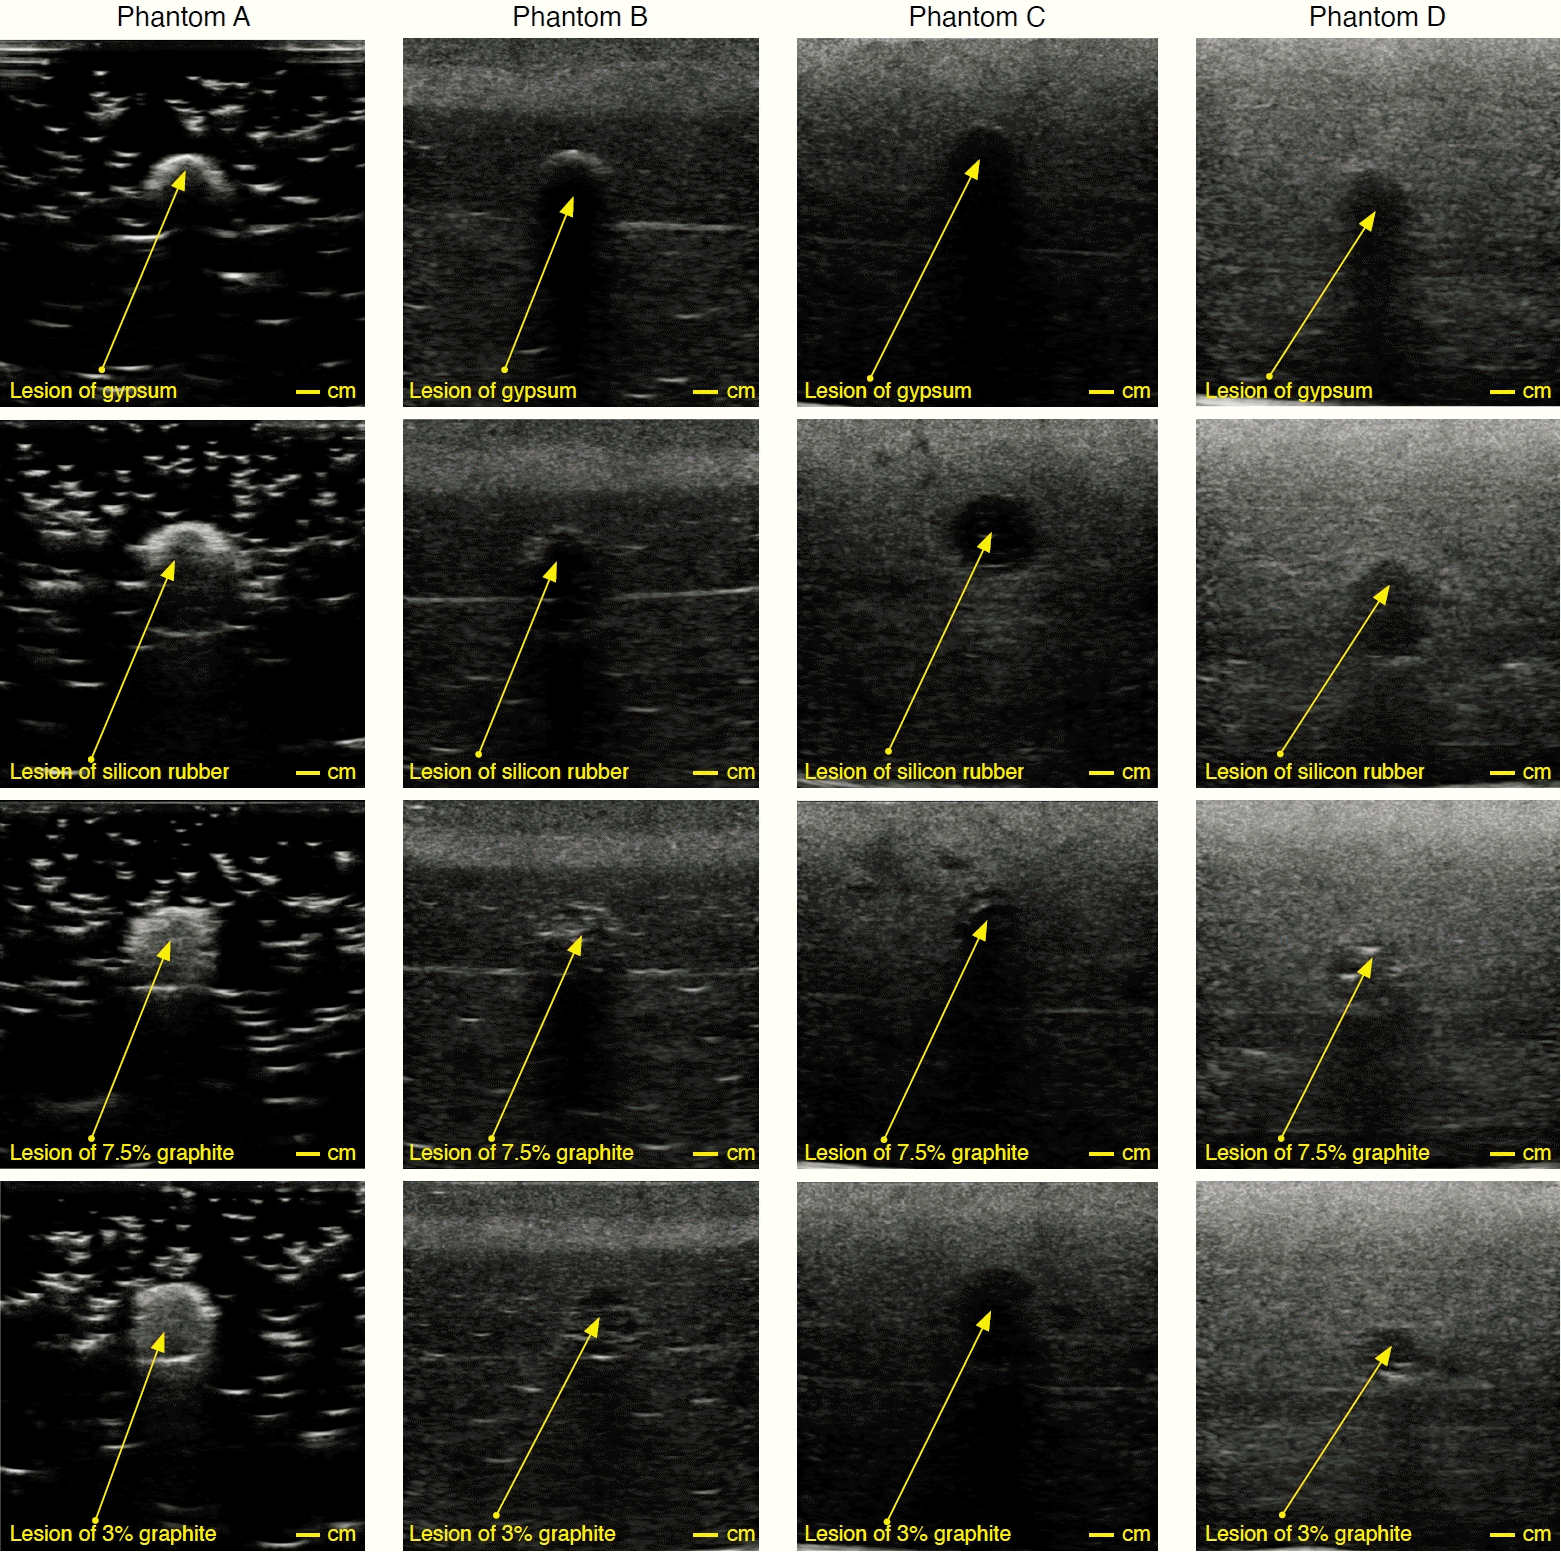

Acquisition and Validation of the Phantoms

Fig. 7 presents B-mode ultrasound images of phantoms A-D, consisting of background phantoms with glycerol concentrations from 0% to 15% and lesions sized 0.85 cm. Phantom A predominantly showed a dark appearance, indicating anechoic characteristics with minimal echo returns. Conversely, phantoms C and D appeared progressively grayer, indicating increased echogenicity with glycerol addition. Pixel values increased from 13.98±12.16 (phantom A), 33.02±10 (phantom B), 44.80±8.84 (phantom C), to 62.99±5.07 (phantom D).

Phantom A ultrasound images demonstrated a non-uniform pixel-value distribution within the background phantom, characterized predominantly by black and white specks due to incomplete mixing of PVC and DOP, which formed white speckles. Despite this, each lesion in phantom A provided images with greater contrast relative to the background phantom, indicating the presence of echoes. Fully dissolved PVC and DOP mixtures produced primarily anechoic ultrasound images. Conversely, phantoms B-D, which included glycerol, yielded images with increasingly uniform grayscale appearance compared to phantom A. Adding glycerol enhanced echogenicity and improved pixel distribution uniformity (Fig. 7). Pixel-value comparisons indicated that background phantoms B and C closely resembled fat tissue, whereas background phantom D closely resembled breast glandular tissue [39]. Therefore, incorporating glycerol at controlled concentrations allowed specific tissue mimicry depending on clinical needs.

Each phantom included lesions varying in both material composition (four types) and size (three types), all shaped spherically. Gypsum lesions produced dark images with incomplete circular boundaries, due to limited reflection of sound waves back to the transducer. Silicone rubber lesions resulted in dark, fully circular images, demonstrating that gypsum and silicone rubber lesions produced clear anechoic patterns in phantoms B-D. Lesions containing graphite produced hypoechoic patterns. Interestingly, all lesions produced hyperechoic patterns in phantom A (Fig. 7).

Fig. 7.

B-mode ultrasound images acquired from phantoms A, B, C, and D, with glycerol concentrations of 0%, 5%, 10%, and 15%, respectively.

Each phantom included four lesion types of identical sizes.